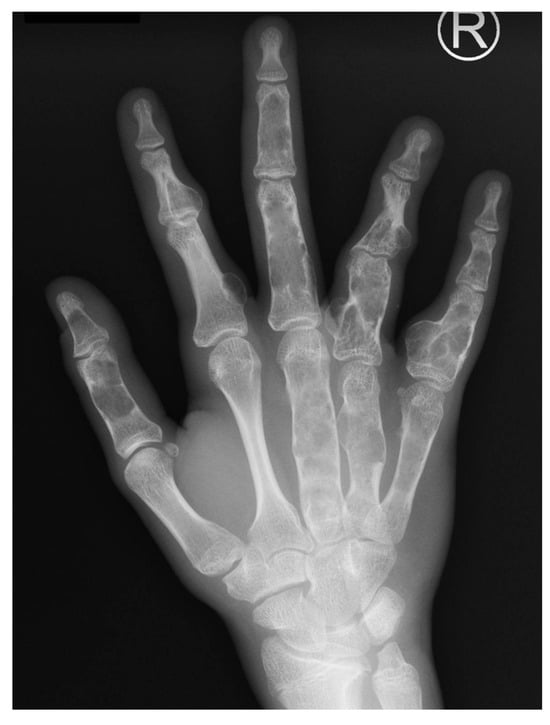

Macrodactyly is characterized by an increase in the size of one or multiple digits in the hand or foot compared to the contralateral or neighboring rays [3]. Excessive growth can occur bilaterally. The affected fingers frequently show asymmetrical deformity, stiffness, limited mobility, discomfort, or pain. Each patient may have a different proportion of overgrowth of bones compared to extensive fat tissue volume. In some children, overgrowth is accompanied by syndactyly, a congenital limb difference where fingers are joined together. Vascular anomalies, metacarpal involvement, or limb hemihypertrophy may also accompany it. Even with preserved function, visual asymmetry may lead to stigmatization and stress for the whole family [4,5] (Figure 1). Children with macrodactyly often struggle with everyday tasks or participation in childhood games. If a foot is affected, one of the first complaints can be a difference in shoe size or a need for custom-fitted shoes. It is worth noting that patients with foot macrodactyly tend to delay consultation despite its more progressive nature [1] (Figure 2).

Figure 1.

Isolated macrodactyly of the little finger of the hand.

Clinical examination of the whole child is crucial to screen for complex conditions. Isolated macrodactyly should be distinguished from an overgrowth of the upper limb with continuous vascular malformation of the thorax. Isolated conditions have to be separated from syndromes. An X-ray of the affected limb usually supports asymmetry in the skeleton; however, in some cases, the soft tissue component can dominate over mildly overgrown bones. Classic radiograms can present joint deformities, osteophytes, and osteoarthritic changes in advanced cases [1]. Magnetic resonance imaging, computed tomography, and vascular studies may be required to assess more complex syndromic cases. The importance of consulting with other specialists cannot be overstated. It is mandatory to rule out a syndromic component of macrodactyly as external asymmetry may only be the tip of the iceberg of a condition, as observed in PROS. As mentioned, confirmation of PIK3CA mutations in biopsied tissue is of significant value. However, PIK3CA mutations are confirmed in only two-thirds of patients. This results from the low detection rate of macrodactyly as an isolated PROS compared to syndromic cases [18]. Therefore, in most cases, the diagnosis is based only on clinical manifestations [19]. The banking of material may benefit future studies as our understanding of overgrowth syndromes will hopefully improve. The prenatal diagnosis of macrodactyly has been reported [20] and theoretically can enhance postnatal vigilance towards syndromic presentations.